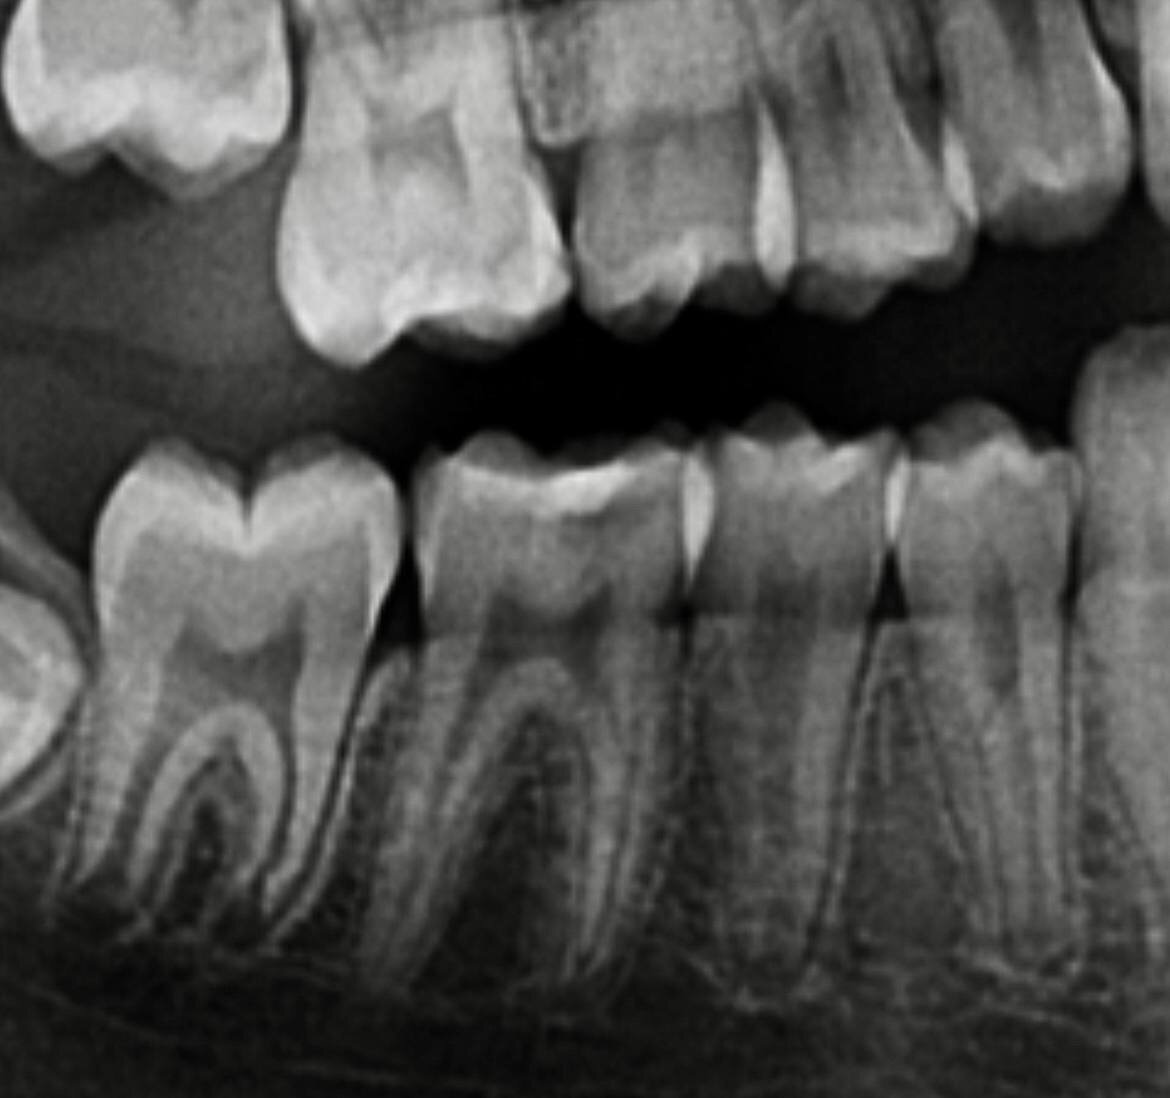

Мальчик, 12 лет. На приеме у меня впервые, до этого был у стоматолога последний раз 2 года назад. Обратился по острой боли, ночная боль в течении 2х дней. Ага, значит с пульпитом имеем дело, воспаленный нерв в зубе так себя и ведет. Там, где указывает, на зубе пломба, причем выглядит очень прилично, со слов мамы зуб лечили 3 года назад.

здесь уточнила область, где проблема

Здесь уже под пломбой мы видим кариозную полость, которая дошла до нерва. Теперь нерв воспален и сигнализирует об этом острой болью. Что делать? Депульпировать зуб, то есть убирать нерв. И это для меня прям грусть-тоска. Когда приходится депульпировать детям постоянные зубы.

Представляете, всего 12 лет, а один зуб уже без нерва, а значит уже не будет иннервироваться и кровоснабжаться, и будет более хрупкий, и значит нужно будет ставить коронку.

Вывод: всем своим пациентам, и маленьким и взрослым, всегда советую раз в год делать у стоматолога общий снимок зубов -ортопантомографию. Потому что иногда оказываются вот такие сюрпризы под старыми пломбами.